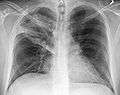

- Normal AP CXR

AP CXR showing left lower lobe pneumonia associated with a small left sided pleural effusion

AP CXR showing right lower lobe pneumonia

AP CXR showing pneumonia of the lingula of the left lung

Right upper lobe pneumonia as marked by the circle.- Left upper lobe pneumonia with a small pleural effusion.

- Right lower lobe pneumonia as seen on a lateral CXR